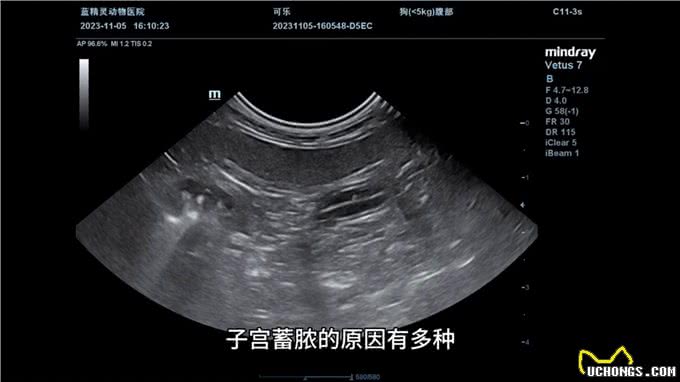

子宫蓄脓的原因有多种,包括母犬发情期接近尾声时,由于雌激素作用导致子宫内膜抵抗细菌能力减弱,细菌到达子宫引起局部感染;或者绝育手术未能将卵巢切除干净,留在体内仍能产生激素的残余组织;另外一些品种的狗狗患子宫蓄脓的几率较高,如万能梗、圣伯纳德、伯恩山犬、查理王、小猎犬、牧羊犬、金毛猎犬等。